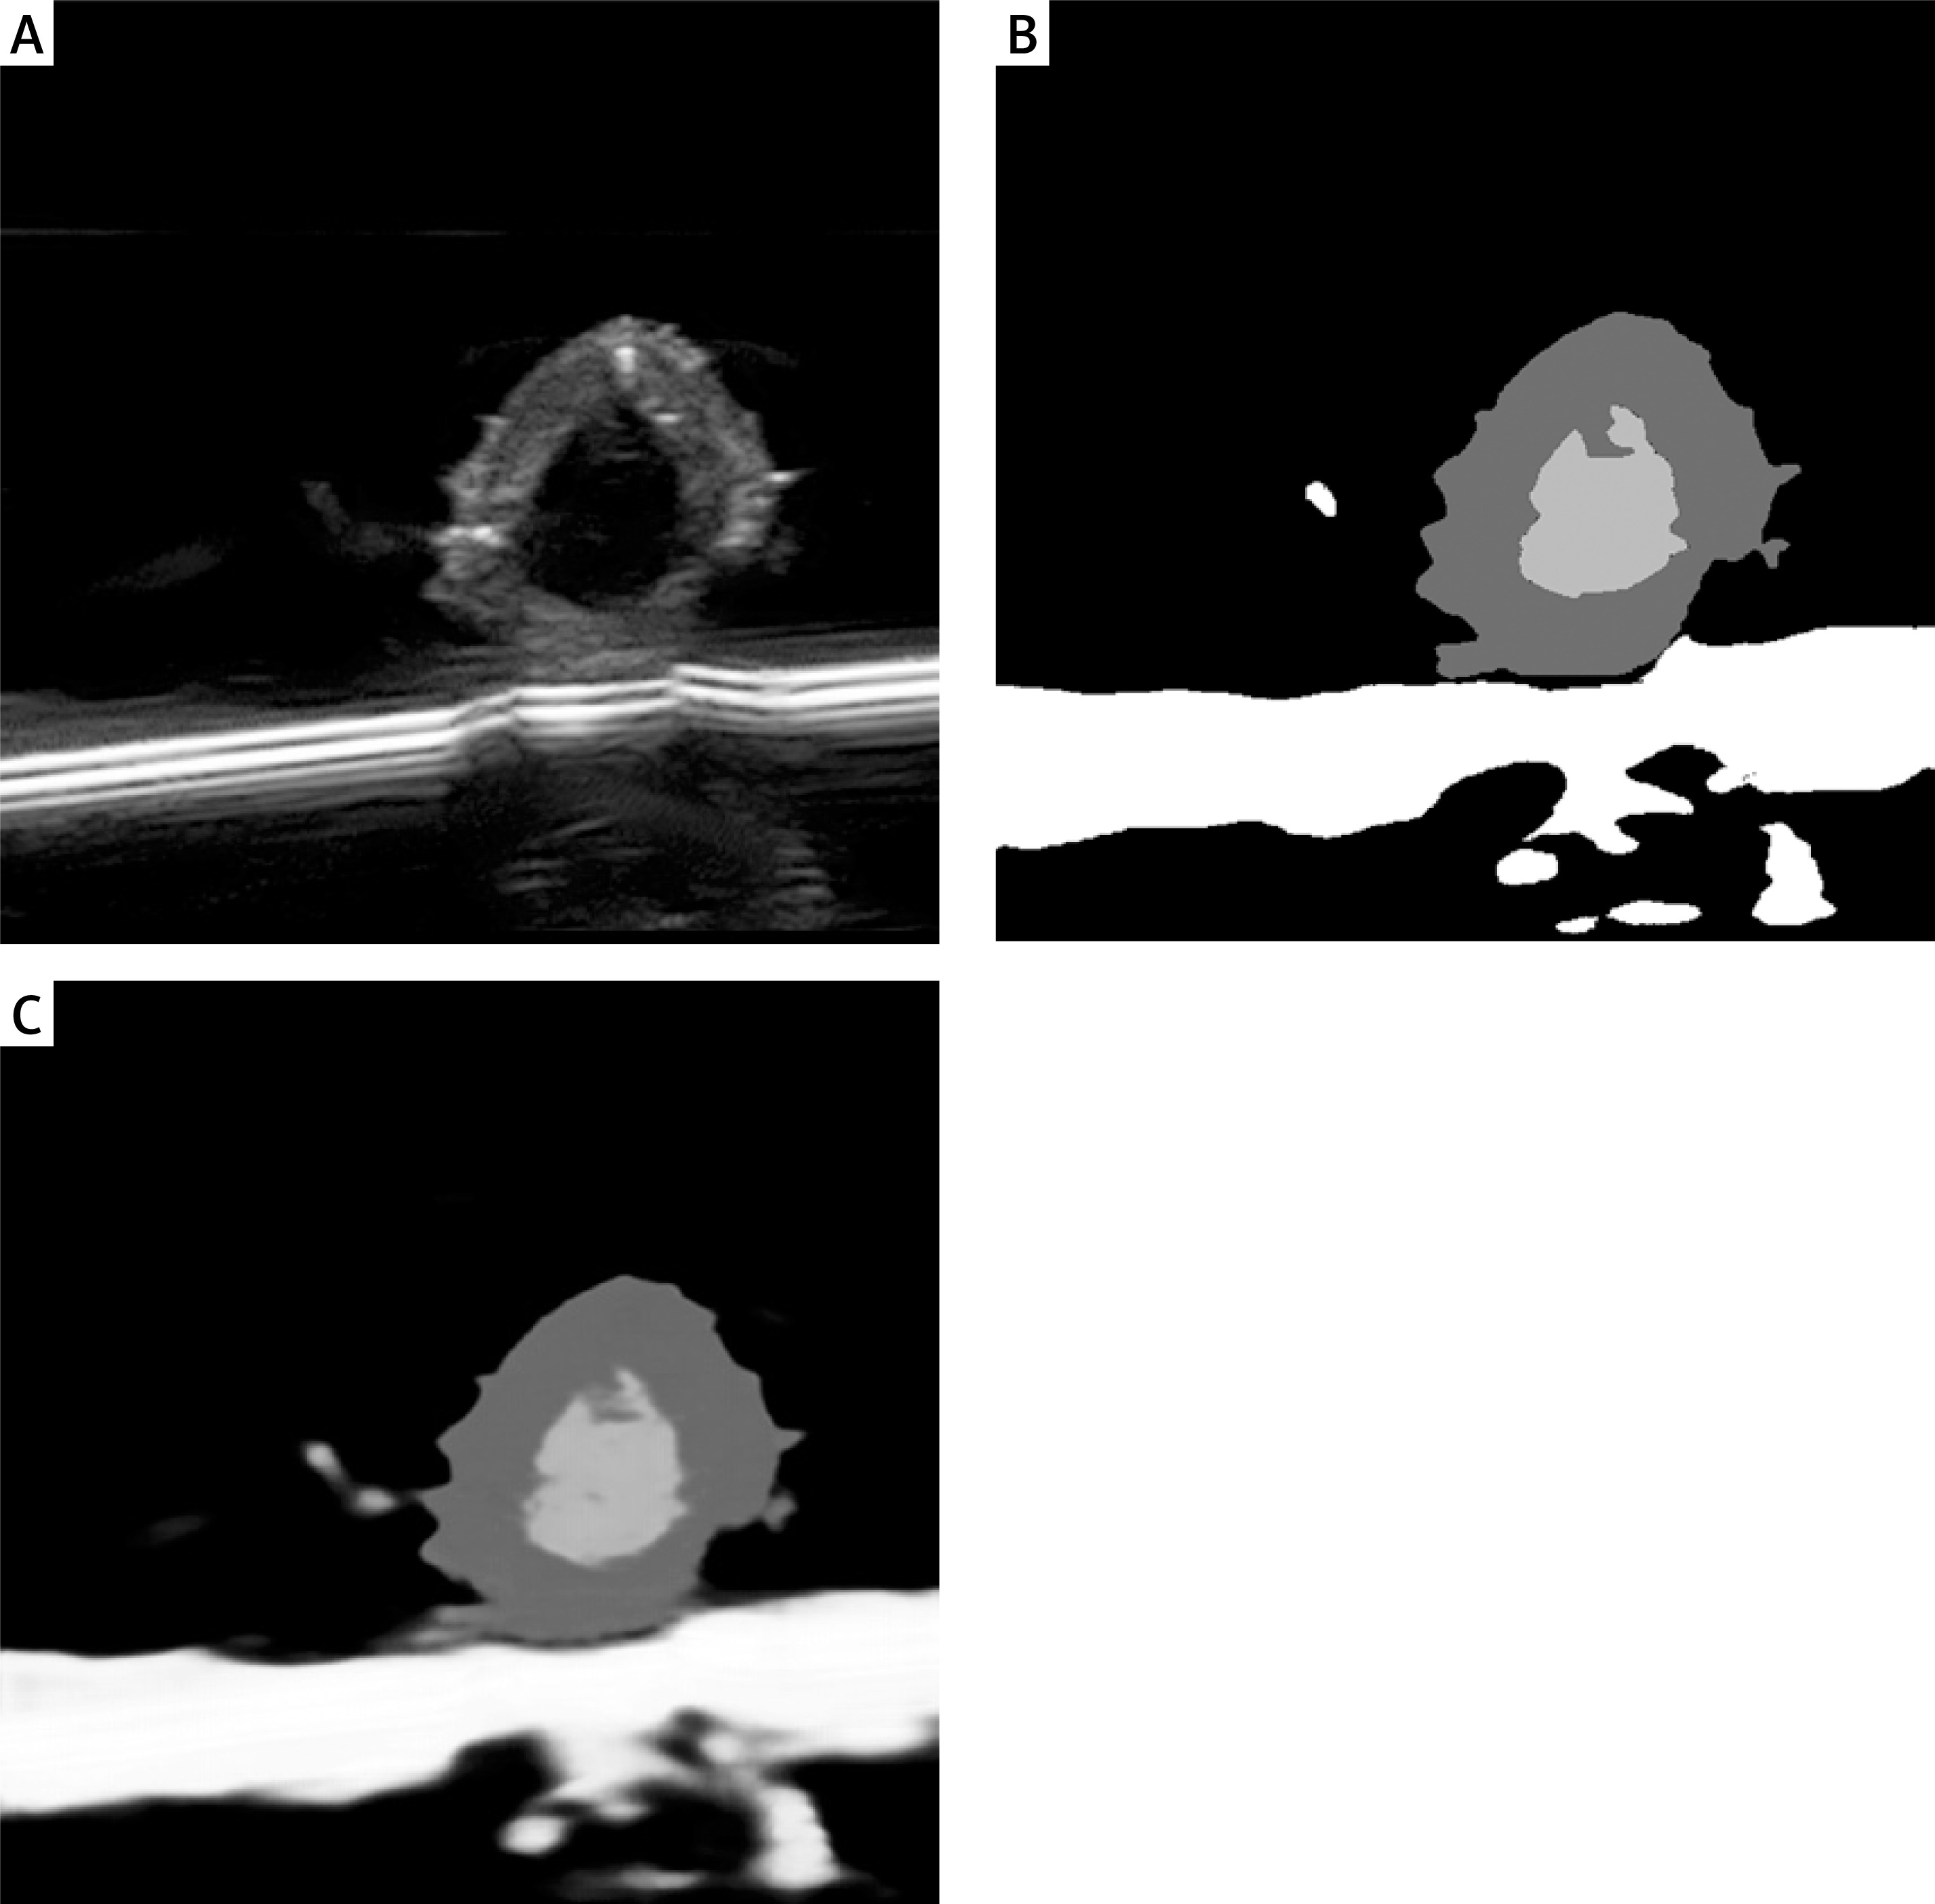

Precise segmentation of arterial lesions with the U-Net model

The U-Net model was applied to segment arterial lesions, achieving an 88% segmentation accuracy (Dice coefficient) on the test set. The results demonstrate the model’s effectiveness in identifying both the core and peripheral areas of atherosclerotic plaques. The introduction of an attention mechanism further enhances the model’s ability to capture subtle lesion details, particularly in complex vascular structures. Figure 2 illustrates the segmentation performance of the U-Net model, with the overlap between the model-generated results and expert annotations exceeding 85%.